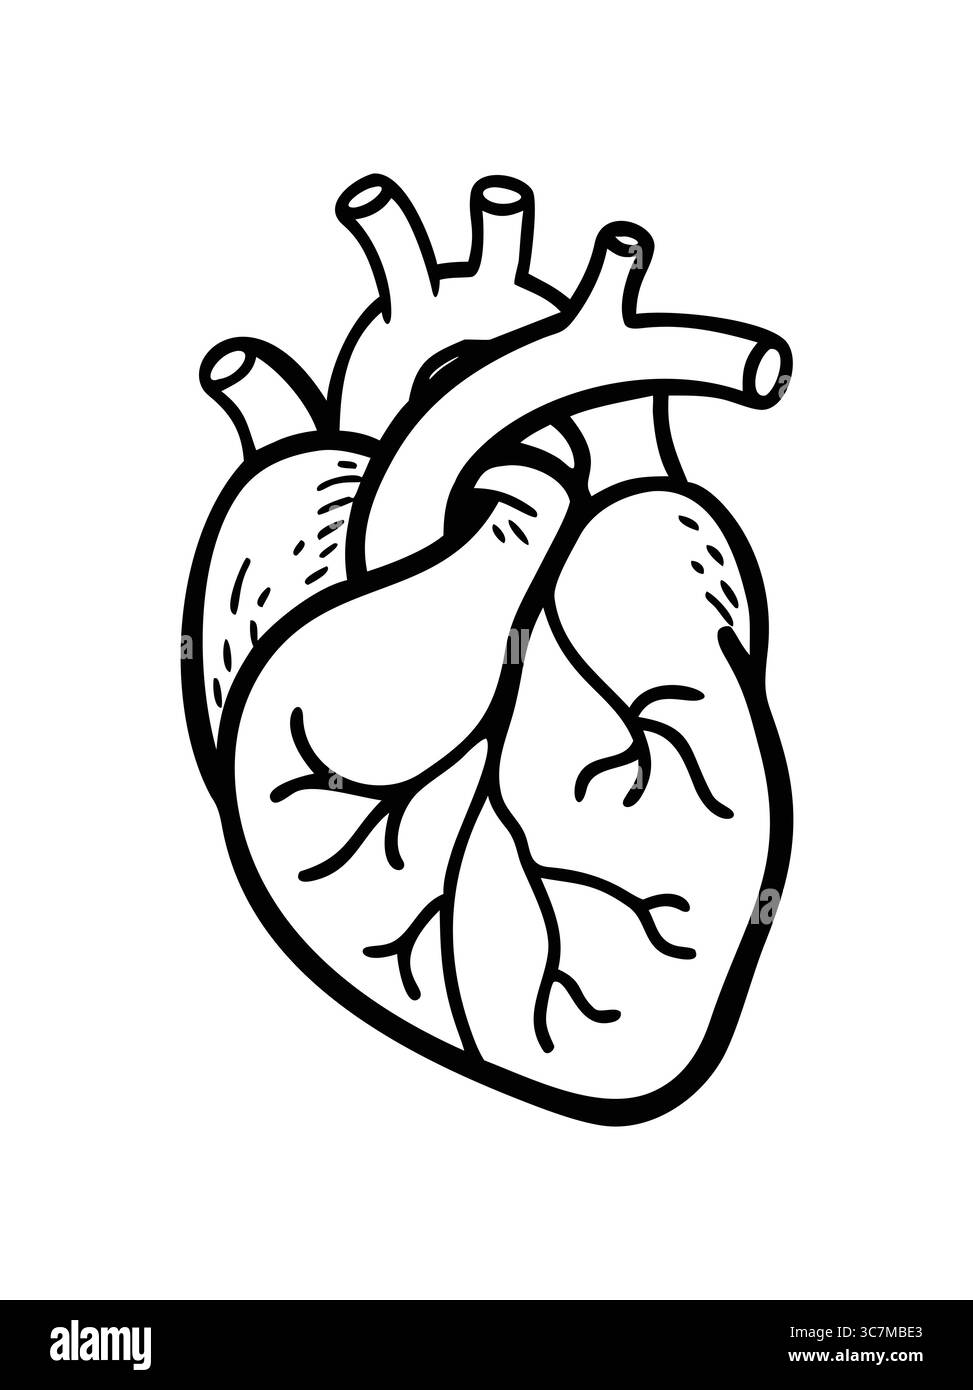

Line art heart anatomy illustration Stock Vectorhttps://www.alamy.com/image-license-details/?v=1https://www.alamy.com/line-art-heart-anatomy-illustration-image693165371.html

Line art heart anatomy illustration Stock Vectorhttps://www.alamy.com/image-license-details/?v=1https://www.alamy.com/line-art-heart-anatomy-illustration-image693165371.htmlRF3C7MBE3–Line art heart anatomy illustration